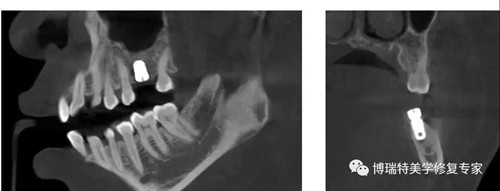

口腔数字化趋势下,CBCT替代全景机和传统CT是大趋势。牙科高速发展的核心业务正畸和种植,都需要对于口腔内部进行精确地三维建模,描绘清楚口腔内血管位置和牙颌骨厚度,因此随着正畸和种植业务渗透率提升,口腔诊所未来离不开 CBCT。

植体周围无阴影,植体螺纹清晰可见

清晰的3D影像为实现数字化精准治疗保驾护航

自1971年第一张人脑CT图诞生至今,技术革命在不断快速迭代。智能3D全景可以帮助医生便捷直观地发现多种牙齿隐患问题,医患沟通变得简单且高效。OnDemand 3D后处理软件直接模拟真实种植场景,使得医患沟通更直观,手术更安全,患者更信任。